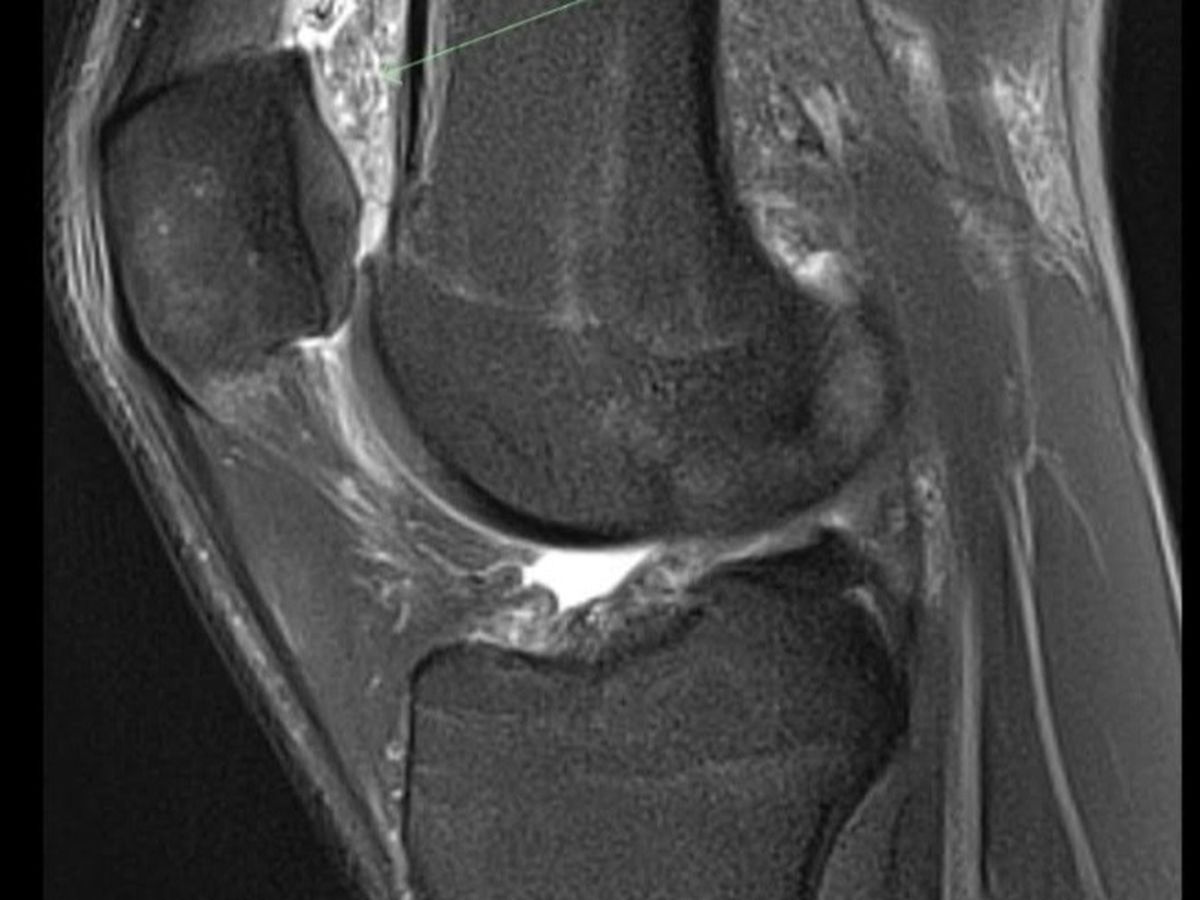

I was hired by Dan Bilzerian and worked for him for several years. If you know who Dan is, you know the lifestyle can be pretty insane. The hours were absolutely insane. But, I loved it. My knees? Not so much. I had some MRIs done and the results were the worst case scenario. I had ACL, MCL, PCL tears and meniscus tears. I was told that I should get into the doc's office ASAP and get it taken care of. As soon as I set my appointment, I was let go from work. Needless to say, I did not go through with the surgery. I didn't have the financial means to do it.

My most recent MRI in February gave me hope. With putting a lot less stress on my knees, I have a lot less to deal with. Pretty much all of the tears have naturally healed, which I'm STOKED AF for. But, it left quite a bit of scar tissue and this wonderful Baker's Cyst.

Having this Baker's Cyst in my knee makes it to where I can't bend my knee fully. It stops my knee at a 90° angle. UPDATE: It's actually pieces of bones that have generated that stop my knee from fully bending and extending, that was the worst case scenario. That makes life pretty damn hard.